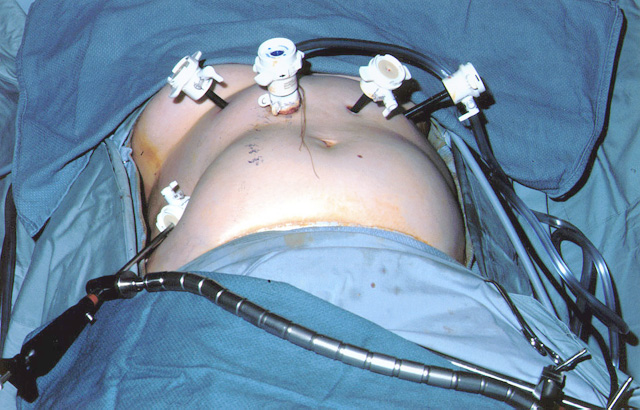

| Figure 2: Laparoscopic port-site placement for repair of giant paraesophageal hernia. |

The patient is positioned supine on the operating table, and the surgeon works from the right side with the assistant on the left. Four 5 mm and one 10 mm laparoscopic ports (Versaport, United States Surgical Corporation (USSC); Norwalk, CT) are placed in the upper abdomen (Figure 2). The left lateral segment of the liver is retracted anteriorly with a 5 mm flexible retractor (Snowden Pencer, Genzyme; Tucker, GA) and secured to a stationary holding device (Mediflex; Islanda, NY).